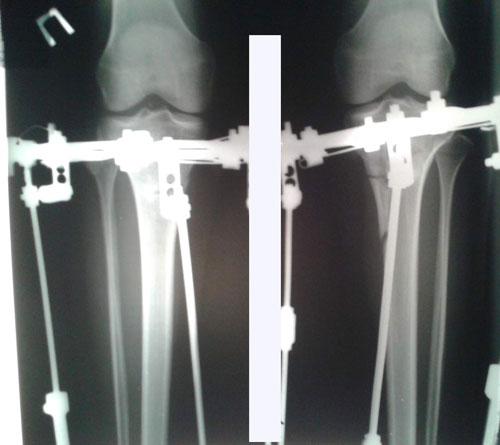

Дата операции 08.10.2015г.

Дата снятие аппаратов 11.12.2015г.

Срок лечения 62 дня.

1,5 МЕСЯЦА с момента снятия аппаратов.

Здравствуйте, А.! Сращение железное, ножки в норме. Вы можете ходить на любой вид спорта, фитнеса, каблуки и т.д. Исключить: беременность в первые 6 месяцев с момента снятия аппаратов.